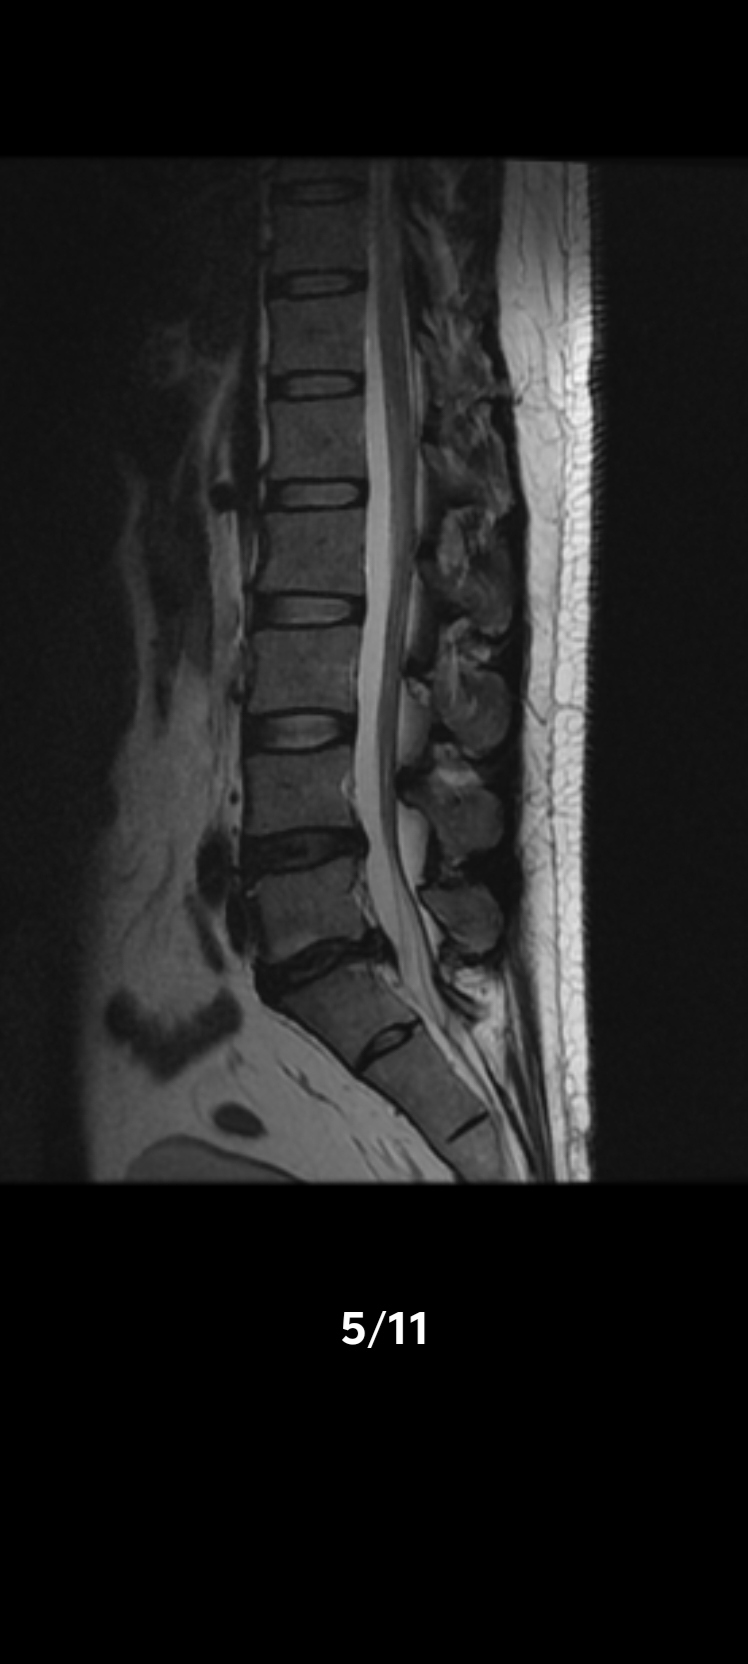

核磁影像终板炎腰痛解析